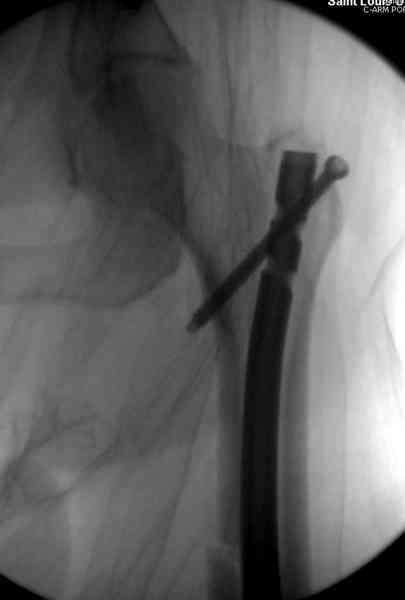

В первый же день произведено антеградное штифтованием DePuy Trochanteric Nail.

На второй день (7) обнаружен пропущенный перелом,

и проведены шурурпы через и спереди штифта без удаления.

Послеоперационные снимки